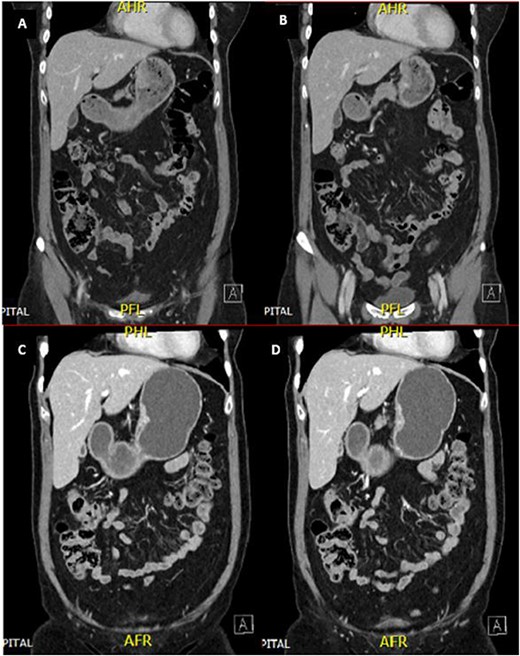

A 65-year-old female was referred to the general surgical outpatient clinic with a 6-month history of epigastric pain and dyspepsia. The patient’s only other medical history was eczema. Physical examination revealed a soft abdomen with no palpable mass. A 10 cm fungating, malignant appearing mass was identified along the gastric lesser curvature on upper gastrointestinal endoscopy (Fig. 1). Histopathology of the biopsied mass demonstrated spindled and small round blue cell tumor with immunohistochemistry staining consistent with Ewing-like sarcoma. Computed tomography (CT) of the abdomen and pelvis showed an enhancing nodular lesion with central calcification and an indeterminate 4 mm lymph node along the lesser curvature of the stomach which raised concerns for gastric malignancy (Fig. 2). Intense fluorodeoxyglucose (FDG) uptake was noted along the lesser curvature of the stomach on staging positron emission tomography (PET) (Fig. 3). There was no evidence of distant metastasis.

(a) PET imaging demonstrated intense FDG uptake along the lesser curvature of the stomach. (b) Interval PET imaging demonstrated reduced FDG uptake at the gastric lesser curvature and reduced gastric wall thickening.

The patient was planned for a 12-week neoadjuvant chemotherapy following discussion with the sarcoma unit and upper gastrointestinal multidisciplinary meeting but her treatment was ceased on the 7th week due to side effects from her chemotherapy regime (Doxorubicin, Vincristine, Cyclophosphamide, Etoposide, Ifosfamide). Interval CT of the abdomen and PET imaging showed reduced FDG uptake at the gastric lesser curvature and reduced gastric wall thickening (Figs 2 and 3).